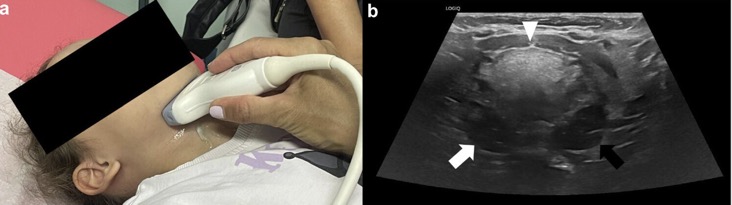

PATHOLOGIES INFLAMMATOIRES

EX: LYMPHOME DE BURKITT